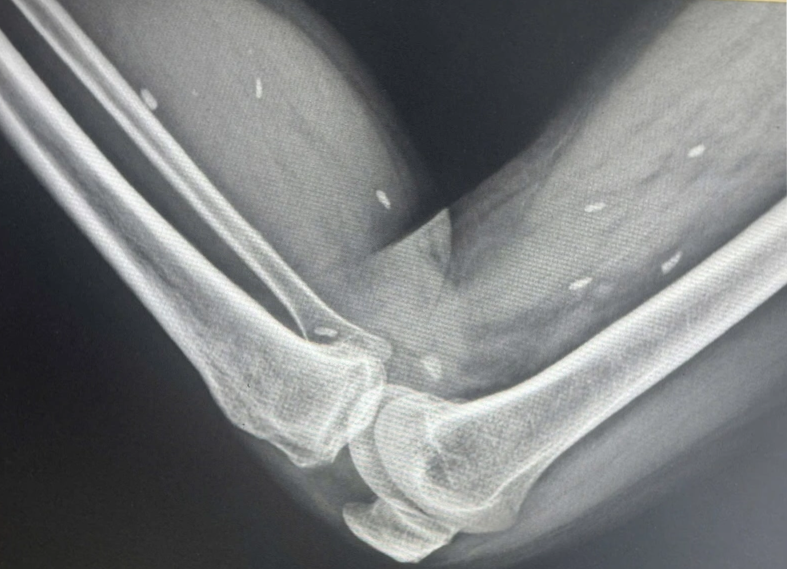

The X-ray results were shocking: multiple cysts, each about the size of a grain of rice, were scattered throughout the soft tissue of the patient’s thighs and calves. Doctors confirmed the findings as classic signs of parasitic cyst infection.